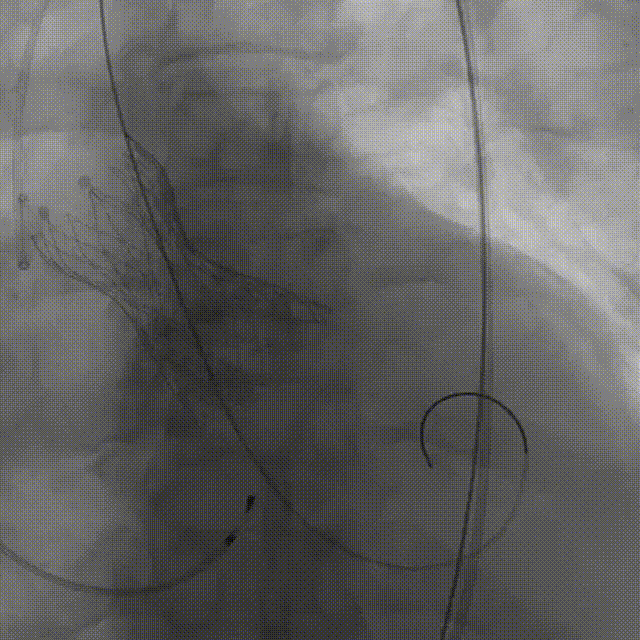

完全释放后造影,膨胀不良,有漏

25mm球囊后扩

后扩后瓣膜形态良好,造影基本无漏